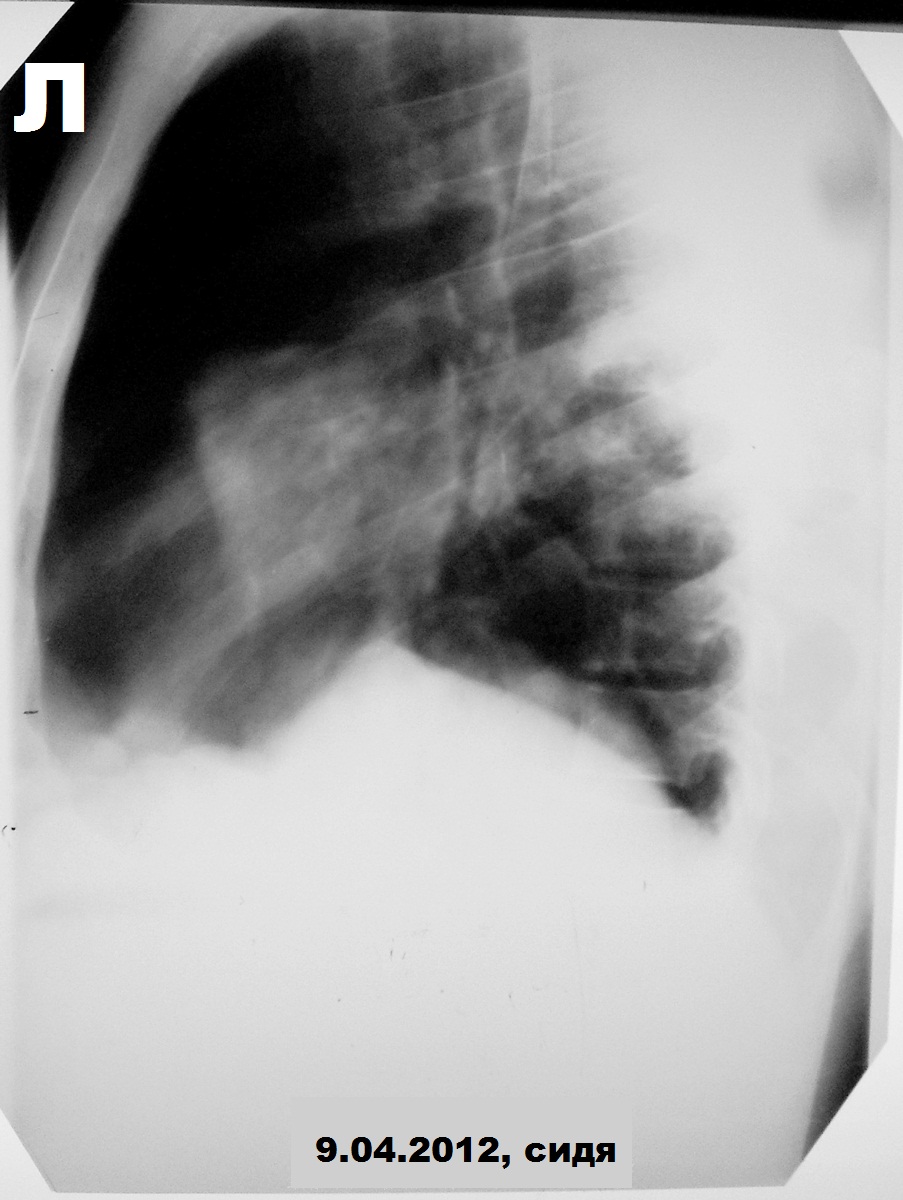

Мужчина, 31 год. ВИЧ+, на учёте 1,5 года, прекратил употреблять наркотические средства около года назад, получает специфическое противовирусное лечение. Носитель гепатита С (обострение в марте, хотели после лечения выписать, но вдруг затемпературил). Динамика с 23 марта по 18 апреля. Состояние с 8 апреля оценивается как тяжелое, боковые снимки с динамической нерезкостью.

Получал антибиотики широкого спектра, на 19-е апреля хотели назначить контроль, но 17-го резкое ухудшение:

Пытаюсь овладеть процессом фотосъёмки легких, не судите строго).

Норма в марте (с усилением рисунка в базальных отделах справа без предыдущих снимков можно поспорить). Затем абсцедирующая пневмония в S6 справа и S8-9-10 слева. Затем напряженный пневмоторакс слева с малым|средним гидротораксом. На контроле левое легкое частично расправлено, уровень жидкости до 6 ребра по задней подмышечной линии. Последний - больших размеров пневмоторакс слева, выраженная эмфизема мягких тканей и пневмомедиастинум.